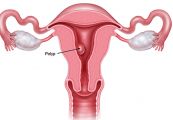

Bệnh tăng sản nội mạc tử cung là tình trạng nội mạc tử cung hay lớp niêm mạc tử cung trở nên quá dày vì tăng trưởng tế bào dư thừa. Mặc dù không phải là ung thư nhưng bệnh này có thể dẫn đến ung thư tử cung trong một số trường hợp. Cùng eLib.VN tìm hiểu bài viết dưới đây để hiểu rõ hơn về bệnh lý này nhé!